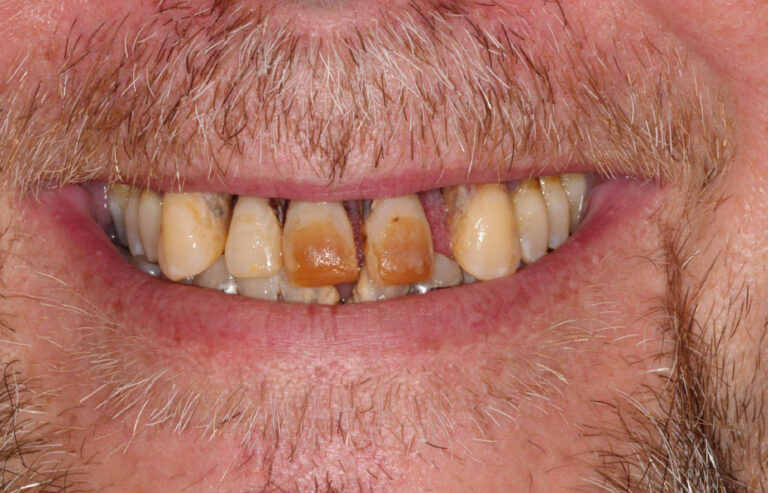

Consultation & 3D Scan

We begin with a comprehensive clinical evaluation and advanced 3D imaging to assess bone quality, anatomy, and functional needs. This allows us to design a fully customized treatment plan from day one.